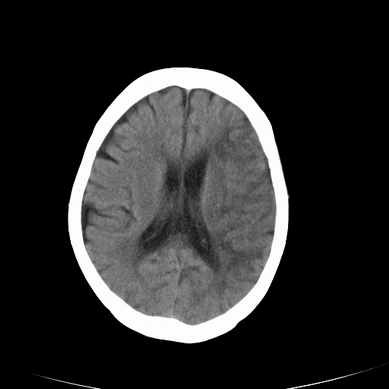

以下是引用jsgdoctor在2008-7-16 23:11:00的发言:[br]左侧大脑中动脉供血区脑梗塞